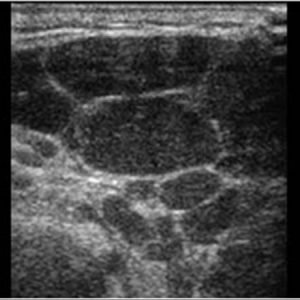

Bệnh Sjögren

Lượt xem: 201» 16-01-2021 -

Bệnh Sjögren

Lượt xem: 152» 16-01-2021 -

Bệnh Sjögren

Lượt xem: 162» 16-01-2021 -

Bệnh Sjögren

Lượt xem: 163» 16-01-2021 -